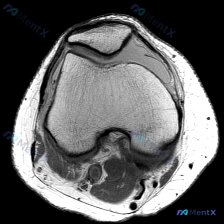

看到这个病例,临床关注点是「膝关节软骨异常」,只拿到了这一张膝关节MRI T1加权轴位图像,整理一下分析思路给大家参考。 一、病例基本影像信息 这是一张股骨远端层面的轴位T1加权图像,先整理一下能看到的信息: 1. 骨结构:股骨内侧髁、外侧髁轮廓清晰,皮质骨连续低信号,骨髓腔内中等信号符合正常表现,...